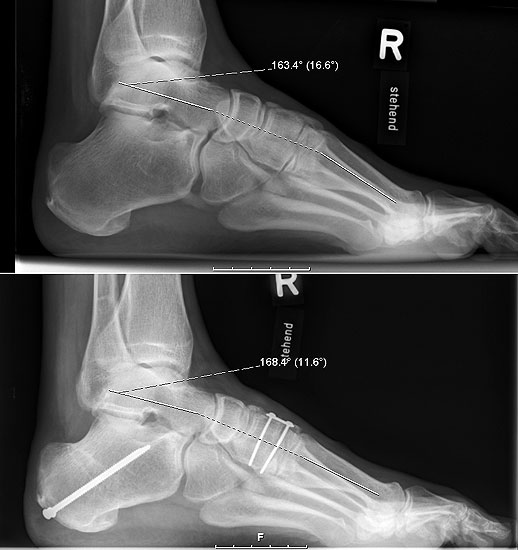

Lateralisierende Calcaneus-Osteotomie (Abb. 2 und 3, Video 2)

Die lateralisierende Calcaneus-Osteotomie ist ein Standard-Operationsschritt bei fast jeder Hohlfuβkorrektur. Der biomechanische Effekt der Osteotomie ist eine Verschiebung des Fersenkontaktpunktes und damit der beim Rückfuβ varus medialisierten Belastungsachse durch das OSG nach lateral. Diese statische Rückfuβ-Korrektur allein ist in der Lage, den bei Pes cavovarus anteromedial erhöhten OSG-Druck, der sehr wahrscheinlich zur korrespondierenden Arthrose führt, zu neutralisieren 7. Zuklappende Osteotomien mit Entnahme eines lateralen Knochenkeils haben sich dabei weniger effektiv gezeigt als solche mit Lateralisation des Tubers. Mit der Lateralisation des Achilles-Ansatzes verringert sich die Inversionskraft der Sehne zugunsten der schwachen Eversion, wodurch gleichzeitig die Prädisposition für Supinationstraumata reduziert wird. Neben der klassischen Dwyer-Osteotomie (Entnahme eines lateralen, vertikalen Keils 8 haben sich vor allem die technisch einfache Verschiebe-Osteotomien („sliding osteotomy“) und die Z-förmigen Osteotomien (Pisani 1993, Malerba 9) mit Entnahme eines lateralen Keils aus dem horizontalen Anteil der Osteotomie aber ohne Lateralisation des Tuberfragmentes, sowie die Korrektur nach Hintermann (Knupp 2008) mit zusätzlicher Lateralisation des Tuberfragmentes) durchgesetzt. Bei neutral aligniertem OSG ist keine supramalleoläre Tibia-Osteotomie zur Korrektur des Rückfuβ varus indiziert. Generell sollten Osteotomien gegenüber korrigierenden Arthrodesen der Vorzug gegeben werden. Die im Folgenden beschriebene Verschiebeosteotomie ist technisch einfach und hinsichtlich OSG-Druckneutralisation ebenso effektiv wie die Z-Osteotomien 7.

• Umfahren des Calcaneus mit Hohmann Hebeln und Markieren der Osteotomie mit 2 1.6 Kirschnerdrähten; Kontrolle der korrekten Osteotomie-Ebene im BV, diese sollten, da in der Regel keine Verkürzung oder Verlängerung des Rückfuβes gewünscht ist, in der axialen Projektion genau rechtwinklig zur Achse des Calcaneus verlaufen; seitlich beginnt die Osteotomie proximal etwa 2 cm anterior des Achilles-Ansatzes und läuft etwas schräg nach distal-anterior.

• Kontrolle der korrekten Schraubenlage im BV (Abb. 3).